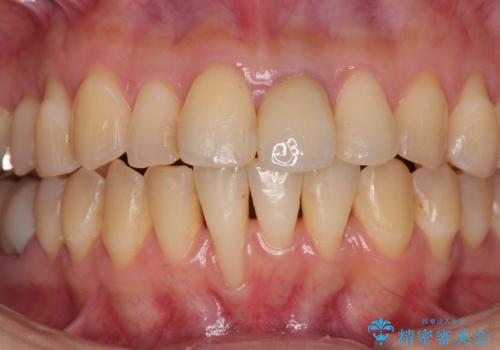

- 他院で矯正治療を終えた結果、下顎前歯の歯肉が退縮してしまい、歯根が見えていることが気になるとのことで来院された患者様です。

歯肉退縮に対して、上顎からの結合組織移植術(CTG)により、歯根の被覆を行うとともに、歯肉の厚みを増すことで将来の退縮リスクを抑制することとしました。

一度の処置で大幅に露出部の被覆に成功しましたが、更なる厚みと被覆を希望されて2回目の処置を行いました。

歯根部周辺の歯肉が非常に分厚くなり、今後の退縮リスクが大きく軽減されました。